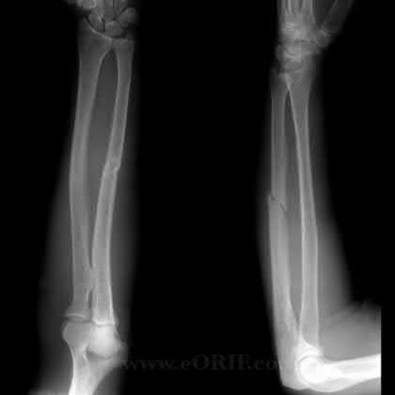

A 12-year-old male sustains an ulnar fracture with an associated posterior-lateral radial head dislocation. After undergoing closed reduction, the radiocapitellar joint is noted to remain non-concentric. What is the most likely finding?

In pediatric Monteggia fractures the annular ligament is commonly interposed in the radiocapitellar joint.

Bado initially described and classified Monteggia fractures. The most common injury pattern is an extension type 1 with anterior radial head dislocation and apex anterior ulnar shaft fracture. The apex of the ulna fracture determines the direction of the radial head subluxation or dislocation. Adults typically require ORIF of the ulna. These fractures in children are often treated non-operatively with closed reduction if the ulna fracture is transverse and stable. Type III is the one most commonly associated with irreducibility of the radial head because of interposition of the annular ligament. The incidence of posterior interosseous nerve injury is high with this lesion. The nerve deficit usually completely resolves rapidly and spontaneously.

Tan et al reviewed their treatment of 35 children with Type I and Type III Monteggia fractures. All radial heads were explored and the interposed annular ligament was stretched out of the joint space. They noted that none of the patients had any recurrent dislocation or subluxation.

Ring et al in their review stress the importance of an anatomic reduction of the ulna to restore the reduction of the radial head.